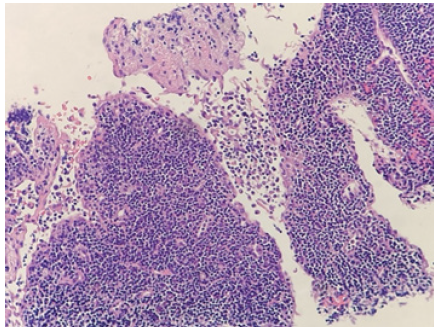

In terms of histology, the affected lymph nodes demonstrate focal, well-circumscribed, paracortical necrotizing changes. High power view of the necrotic foci demonstrates areas of karyorrhexis, pyknosis, karyolysis in addition to scattered fibrin deposits with collections of the crescentic histiocytes (Figure 2&3). Plasmacytoid dendritic cells are often found clustered at the margins of the necrotic foci [9,11-13]. Scanty plasma cell will be seen if not absent. In addition, the absence of neutrophils and eosinophils is a distinguished characteristic of this syndrome. A mixture of large to small lymphocytes are also present. The numerous presences of large lymphocytes with immunoblastic morphology in a background of karyorrhectic debris and scattered tangible body of macrophages, can often mislead the diagnosis towards high-grade lymphoma [9,11-13]. These necrotic foci may be single or multiple with varying degree of necrosis that differ from case to case [7,9,11-13].

Figure 2:High-power view showing the boundary between an areaof karyorrhexis/pyknosis and an area of karyolysis (H&E, original magnification x100)

As the disease progress, the histological appearance will also change accordingly. The early proliferative phase is characterized with follicular hyperplasia and paracortical proliferation of T-cells, B-cells, plasmacytoid monocytes, lymphocytes, and histocytes (Figure 4). Numerous apoptosis in the background of this proliferative picture is also a distinguishing feature. As the disease progress to the later necrotizing phase, the histological appearance will progressively change to show necrosis with the absence of neutrophil infiltrate. The presences of numerous crescentic histocytes with or without phagocytosed debris is a distinct feature of the necrotizing phase as well as Kikuchi-Fujimoto disease itself. Finally, with or without necrotic foci, the presence of foamy histocytes indicate the categorization of xanthomatous phase [9,11-13].